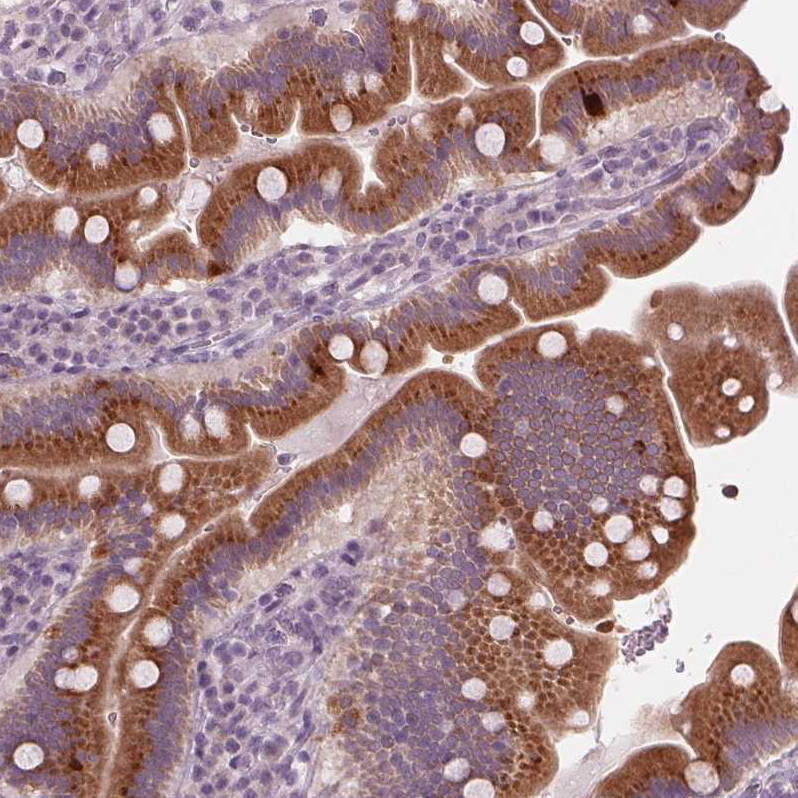

Immunohistochemical staining of human small intestine shows moderate granular cytoplasmic positivity in glandular cells.